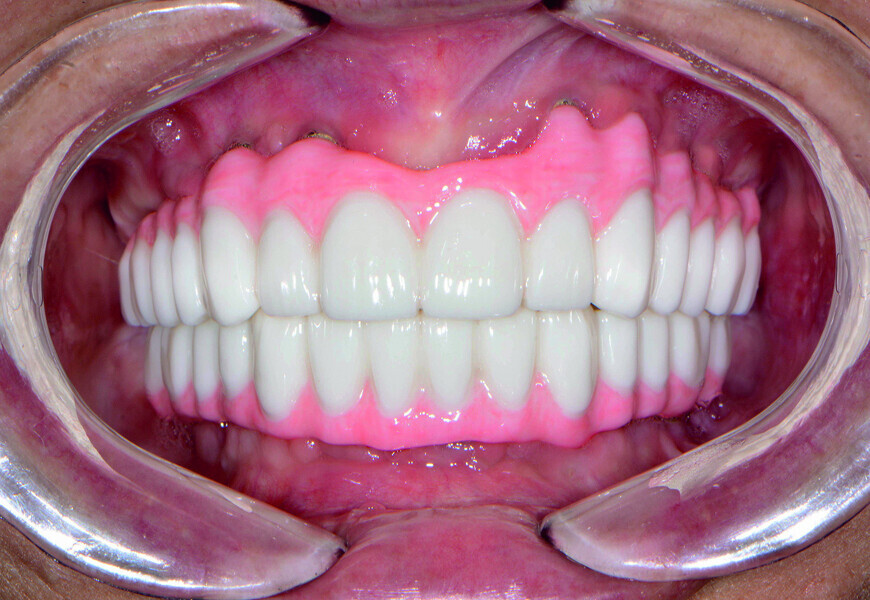

Fig. 21: Post-op retracted open-bite view.

Fig. 22: Post-op retracted closedbite

view.